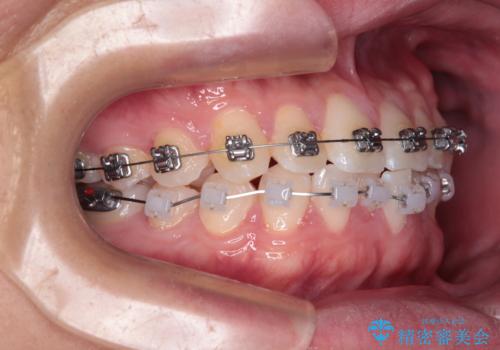

・費用と期間を抑えるために、多少目立っても効率の良いメタルブラケットを使用

・奥歯のシザーズバイト改善には、口蓋側にアンカースクリュー(TAD)を設置し、矯正用ゴムで内側に牽引

・捻転した第二小臼歯は、ワイヤーと矯正用ゴムの力を用いて正しい位置へ回転移動

**前歯のデコボコ(叢生)**が整い、歯列全体が美しく改善

シザーズバイトの奥歯も正常なかみ合わせに改善

捻転歯も回転が修正され、全体的に清掃性・咀嚼効率が向上